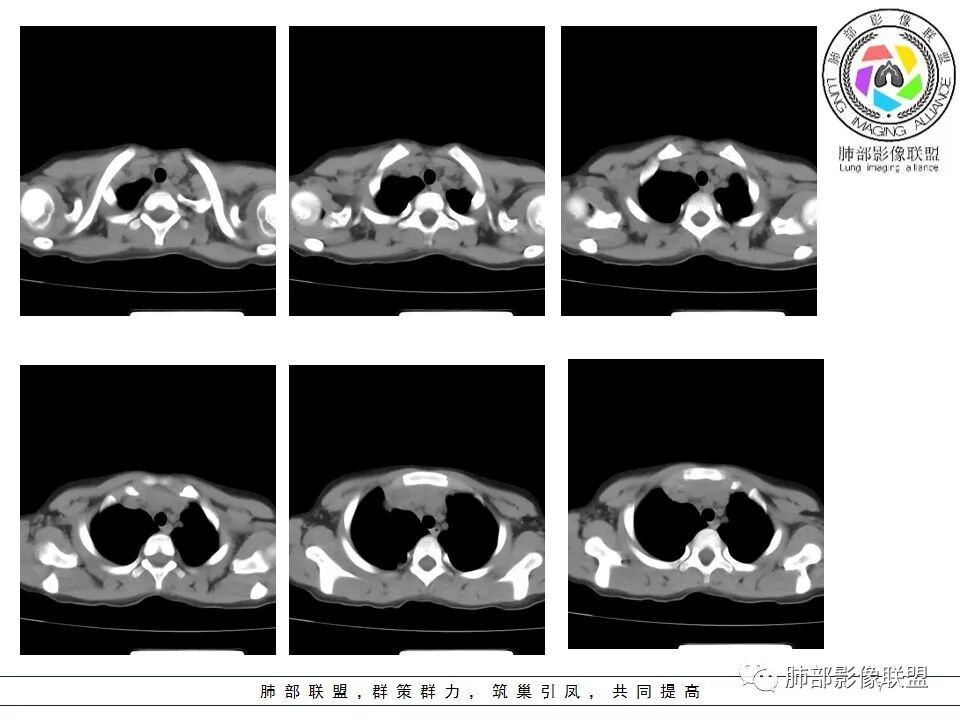

一切∮随缘: 前纵隔偏右侧实性占位,向右肺挤压,右肺膨胀不全,右侧胸水,心包似乎也有胸水,病灶较大无增强,平扫密度欠均匀,内部似可见低密度坏死及高密度钙化影,年轻男性,考虑恶性,生殖细胞肿瘤(精原细胞瘤?恶性畸胎瘤?),鉴别神经母细胞瘤,肺母细胞瘤,PNET?

秦化君: 右前上纵隔软组织密度肿块,边缘部分清晰澎隆,与血管及心包间界线不清,密度较均匀。挤压相邻肺组织形成膨胀不良,侵及胸膜形成胸腔积液。双肺内见随机分布结节。考虑纵隔恶性占位(肺及胸膜转移),生殖细胞瘤,畸胎瘤,淋巴瘤。建议穿刺活检。

放射线 (王秀仙): 右侧前纵膈巨大肿块,与纵膈大血管分界不清并受压,右肺组织受压膨胀不全,密度不均,内可见高密度钙化及低密度坏死区,双肺多发结节状转移灶,右侧胸腔积液,年轻男性,考虑生殖细胞肿瘤,精原细胞瘤可能性大。

右前纵隔巨大软组织肿块,主要偏向右侧生长,边界不清,密度不均匀,内见大片状低密度坏死区及散在钙化灶,未见骨骼影及脂肪密度影。、双肺随机分布的转移瘤结节,右肺肺不张及右侧胸腔积液,提示恶性肿瘤病变伴双肺及胸膜转移。